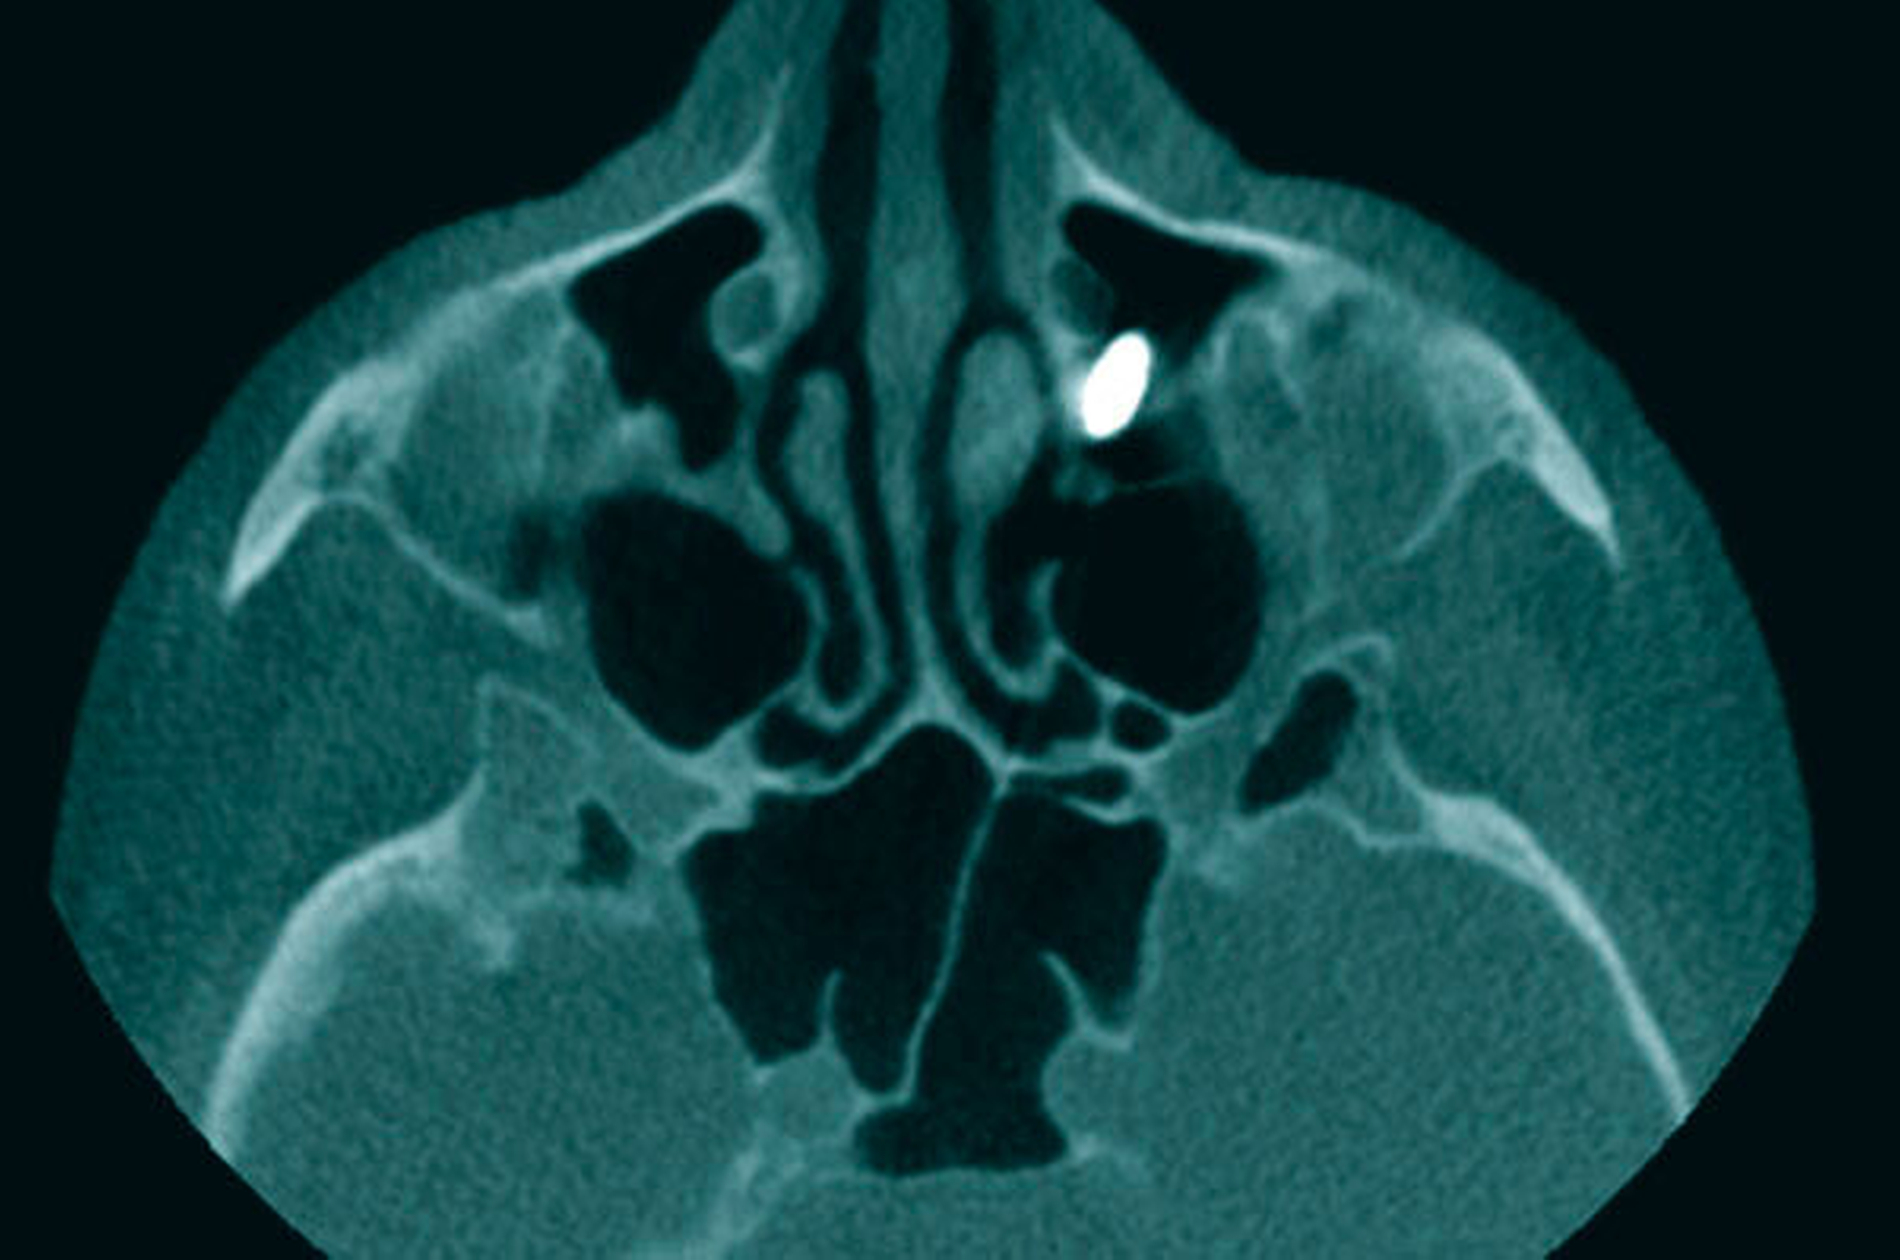

Es folgte die Planung zur operativen Entfernung des Fremdkörpers in Intubationsnarkose über ein enorales Fenster zur Kieferhöhle. Nach Präparation eines mukoperiostalen Lappens über einen marginalen Zahnfleischrandschnitt wurde minimalinvasiv mittels Piezosurgery® (mectron, Köln) ein Knochenfenster zur Kieferhöhle angelegt. Mit dem Endoskop (30grad Optik, Karl-Storz, Berlin) zeigte sich das Ostium naturale offen und frei von dem radiologisch hier lokalisierten Fremdkörper. Dieser befand sich nun im Kieferhöhlenboden (Abbildung 3) und ließ sich komplikationslos bergen (Abbildung 4). Die Wunde wurde mehrschichtig geschlossen.